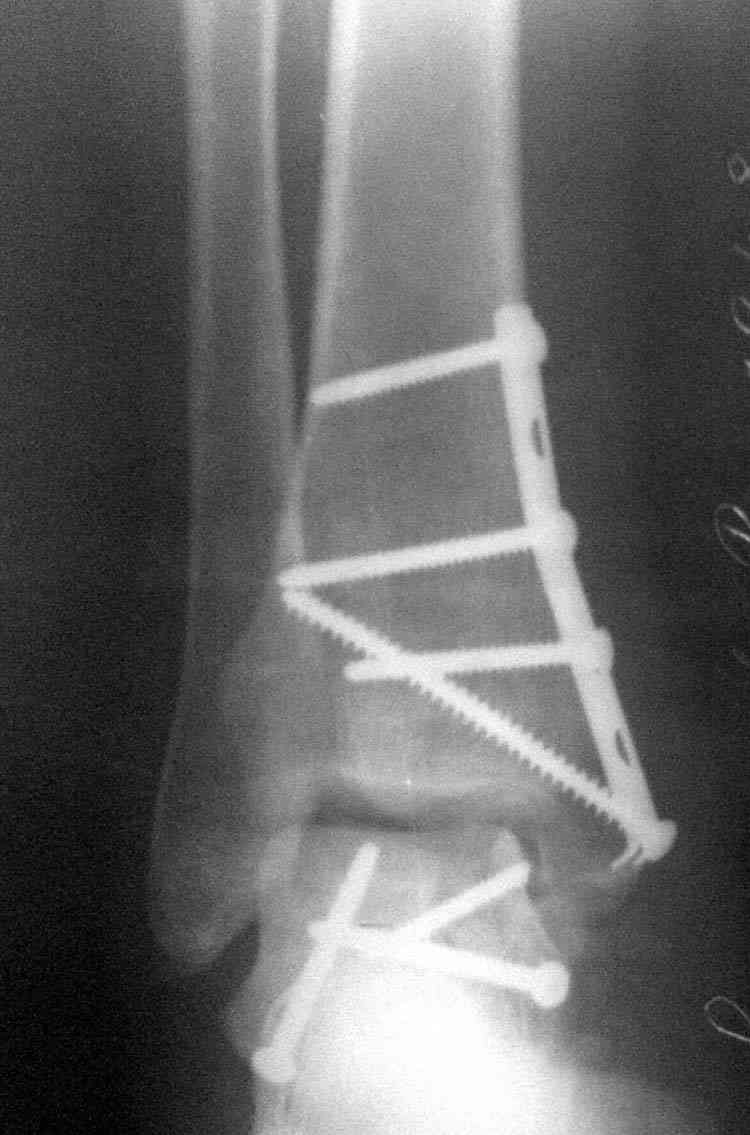

Решили не связываться с остеосинтезом, а сделать сразу берцово-пяточный блок. Снимки в приложении.

По завершении удлинения, наверно, заштифтуем.

Комментарии/критика приветствуются.